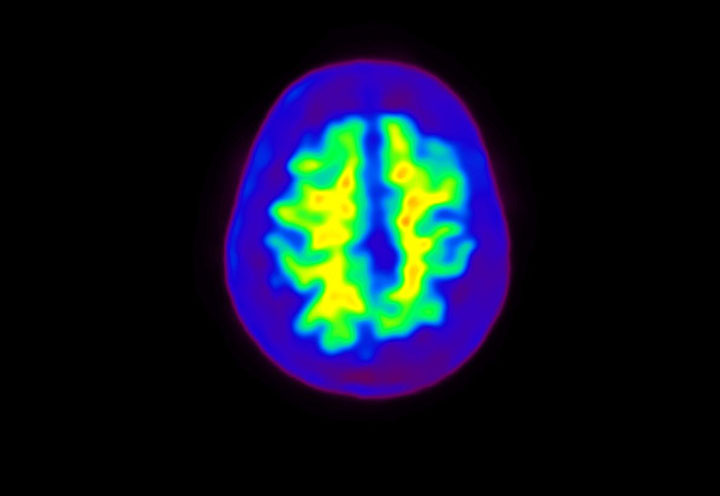

Head / Case4 : Amyloid

Sagittal

Courtesy : Kindai University Hospital

- Imaging protocol

- Injected dose: 3.21 MBq/kg, 18F-Flutemetamol

- Uptake time: 100 minutes

- Scan time: 20 minutes